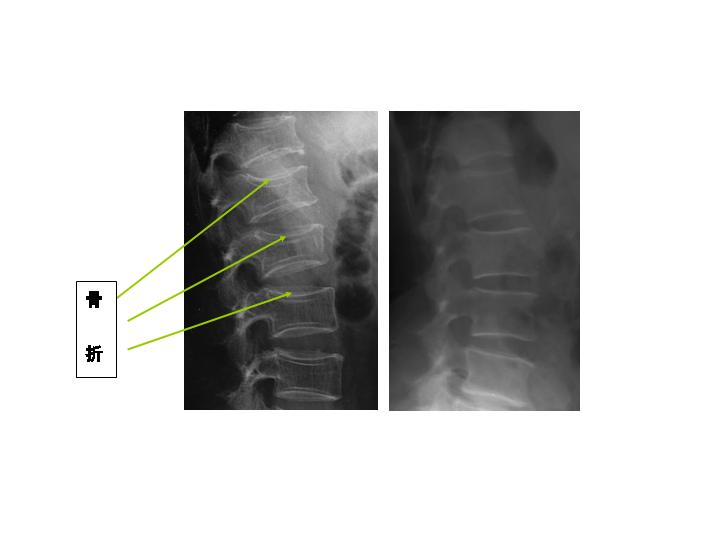

<写真説明>

脊椎X線写真:ステロイド性骨粗しょう症患者(左)と同年代の健常者(右)。左は脊椎の圧迫骨折による変形が見られる。